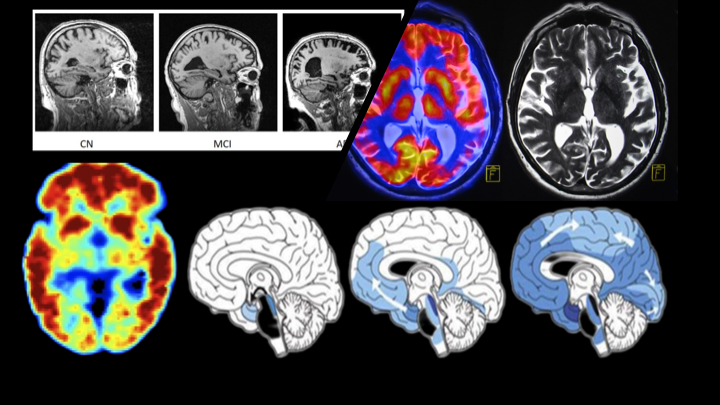

Our work focuses on understanding the stochastic difference between identified peptides from high-throughput mass spectrometry data for applications related to human health, disease, and environment. In addition, our work focuses on understanding brain function in the context of prediction, diagnosis and characterization of biomarkers specific to disorders such as epilepsy, ADHD, Autism, and Alzheimer’s.

Machine-learning models to characterize and predict Alzheimer's disease